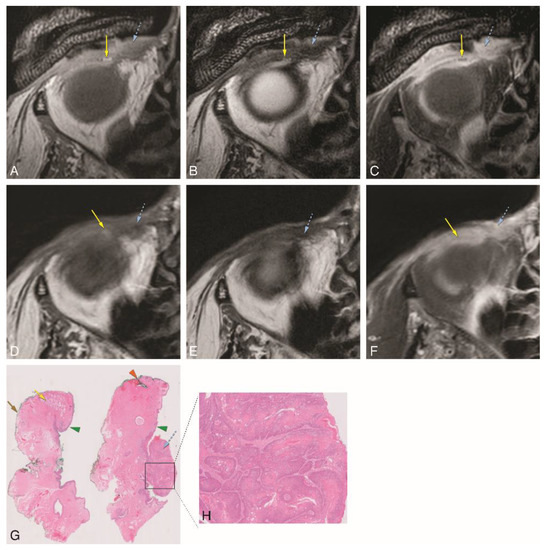

In Group 3, tumor extension of 3 patients with different eyelid tumors was determined through image analysis, both on MRI and CT. The MRI of patient #1 was performed with the dedicated eyelid protocol. It showed a heterogeneous enhancing lesion of the medial aspect of the inferior eyelid on the left (Figure 5). The inferior tarsal plate (Figure 5A,B,D,F) and inferior septum (Figure 5A,B,F) were invaded, and so was the medial palpebral ligament region (Figure 5D,E). The tumor grew posteriorly, invading the orbit and reaching the region of the insertion of the inferior rectus muscle at the globe (Figure 5A–C). Due to the location of the tumor, adjacent to the medial orbital bony wall, a CT scan was also performed, but no bone invasion was noticed either on CT or on MRI. CT was able to demonstrate septal and orbital invasion as well, but underperformed compared to MRI and could not depict tarsal invasion. Due to the presence of orbital invasion, both clinically and radiologically, an eyelid-skin sparing orbital exenteration was performed. The final histopathological examination revealed a well-differentiated squamous cell carcinoma at the epithelium of the palpebral conjunctiva, growing anteriorly invading the septum and posteriorly into the intraorbital fat, surrounded by a diffuse inflammatory infiltrate. No perineural or angioinvasive extension was seen (Figure 5H,I).

Figure 5. A–I: Patient #1 of Group 3 with a squamous cell carcinoma (SCC) of the left inferior tarsal and bulbar conjunctiva (dedicated eyelid protocol). A–C: Sagittals T1-WI (A), T2-WI (B), and contrast-enhanced T1-WI with fat signal suppression (C) showing the tumor (blue dashed arrow) invading the orbit and reaching the region of insertion of the inferior rectus muscle at the globe. D–G: Axials T1-WI (D,F) and contrast-enhanced T1-WI with fat signal suppression (E,G) at the level of the inferior eyelid (slices D and E are superior to slices F and G). Notice the tumor (blue dashed arrow) invading the medial inferior tarsal plate (yellow arrow) and medial palpebral ligament region (white dashed arrow) (D,E), and inferiorly growing behind the septum limit (blue arrow) (F,G). H–I: Histopathological examination hematoxylin and eosin stain (H&E) (0.5×) (H) and histopathological examination H&E stain (5×) (I). Notice the tumor (blue dashed arrow) at the epithelium of the palpebral conjunctiva growing anteriorly and invading the septum and posteriorly into the intraorbital fat (H). Well-differentiated SCC (I). Blue dashed arrow: tumor; orange arrow: orbicularis oculi muscle; yellow arrow: superior and inferior tarsal plates; blue arrow: superior and inferior orbital septa; white dashed arrow: medial palpebral ligament region; yellow star: intraorbital fat; white arrowhead: superior transverse ligament (Whitnall ligament); red arrow: levator palpebrae muscle; grey arrow: superior rectus muscle; white asterisk: inferior oblique muscle; green arrow: inferior rectus muscle.